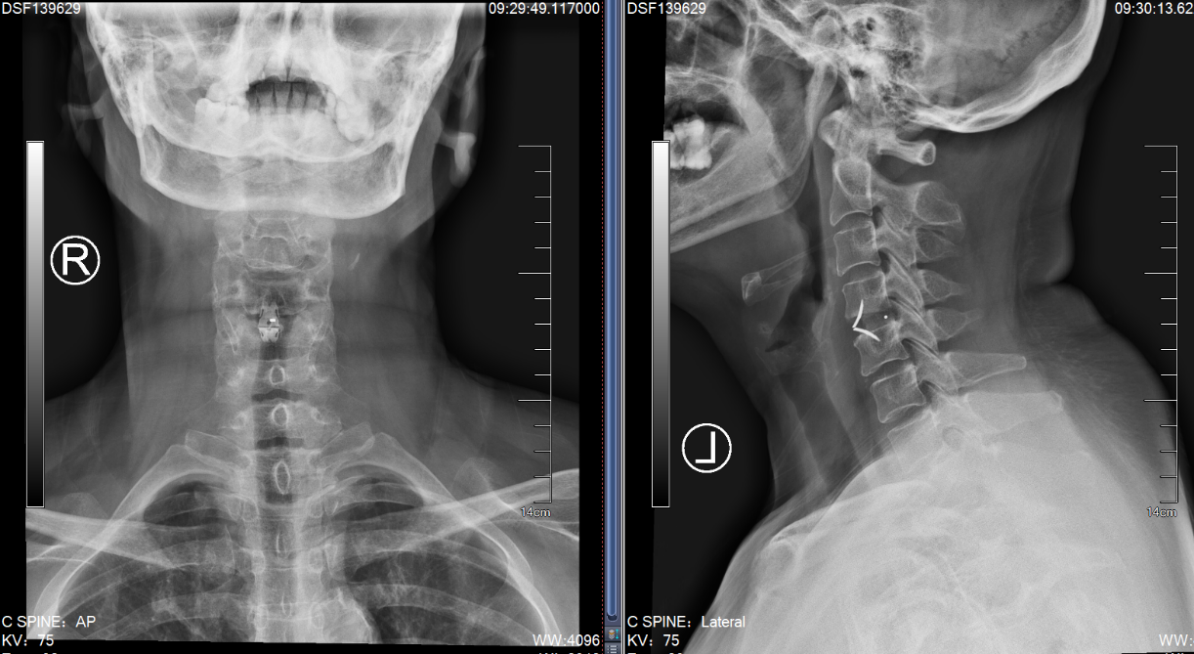

无独有偶,我院骨科还为一对姐弟完成了一组颈椎后路手术。姐弟俩吕艳、吕飞(化名)均患有“颈椎后纵韧带骨化症”。弟弟吕飞今年40岁,是位企业白领。别看他年龄不大,其实已多年饱受颈椎病之苦。由于长期伏案工作,这些年他常常感觉自己四肢乏力,走路像踩在棉花上一般,像系纽扣、写字这样的活动也逐渐无法完成,这让他很是着急。通过亲友介绍,他找到姜为民主任寻求帮助,姜主任在仔细的查体和阅片后,判断吕飞的颈椎后纵韧带骨化节段多,症状重,应当尽早手术,解除对脊髓的压迫。

(颈椎CT提示患者C3-6椎体后纵韧带骨化明显,椎管狭窄显著)

吕飞采纳了姜主任的建议,办理了住院,接受了“颈椎后路椎管扩大成形术”,就是脊柱外科医生俗称的“单开门”手术。该术式可以在扩大颈椎椎管空间,解除脊髓压迫的同时,最大程度地保留患者颈椎的活动度,避免术后颈部僵硬的情况发生。术后,吕飞的症状有了显著的改善,术后一周便顺利出院了,对此他感到非常开心。

(颈椎术后X片:C3-6椎管扩大成形术后)